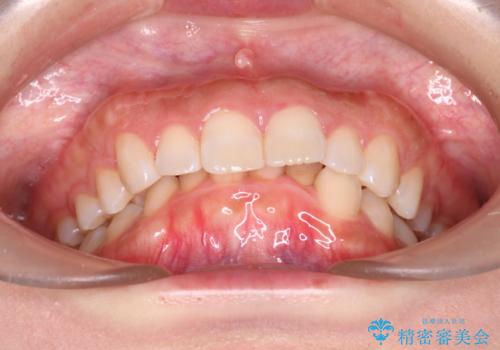

- 上の前歯の出っ歯と前歯の深い咬み合わせを治したいとのことで来院された患者様です。

上顎の歯は後方移動とIPR(歯と歯の間を削る)によって口元が引っ込むように、下顎は歯列全体の拡大とIPRによって上顎とバランスよく咬み合うように設計し、インビザラインにより治療を行うこととしました。

上顎歯列の後方への移動量が多く、右側の奥歯の咬み合わせを改善する必要もあったため、治療には長期間を要しました。